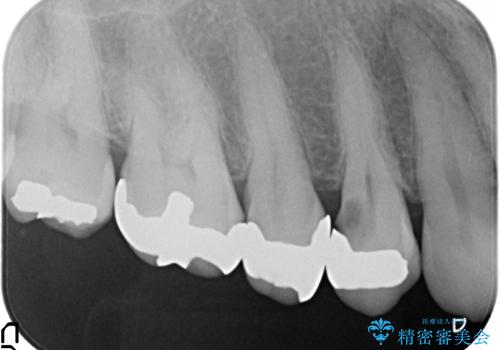

- 右上4番目の歯がなにもしなくてもズキズキ痛むといらっしゃった方の症例です。

検査の結果持続痛も認めたため、虫歯除去後根管治療を行いました。

その後オールセラミッククラウン(エクセレント)による補綴を行いました。